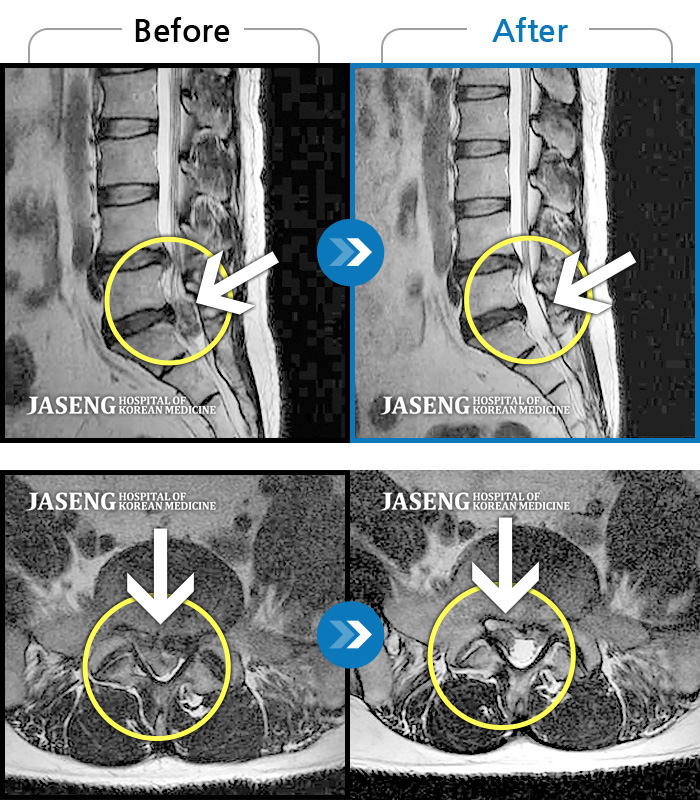

허리디스크

잠실 · 한상욱 원장

우측 엉치부터 우측 다리부터 발끝까지 저리고 아프다. 감각까지 먹먹하다.

촬영시기

2022.04.15 ~ 2022.10.22

2022.12.02